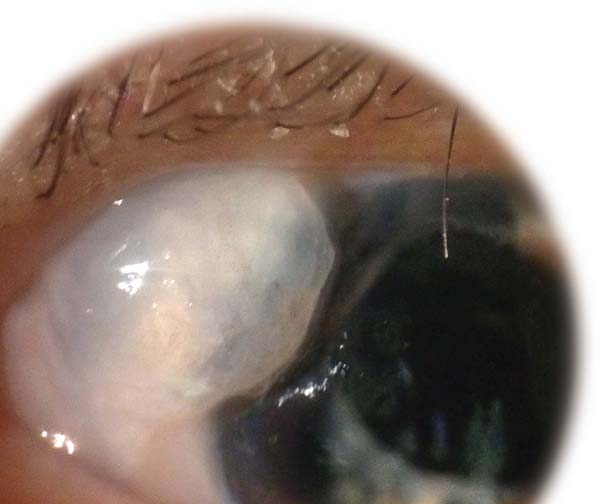

<각막함요, 각막델렌, 각막패임, dellen>

각막함요, dellen 이란

각막 윤부 주위에 불룩튀어난 융기된 병변 혹은 윤부 주위에 염증이 발생하였을 때,

그 인접한 각막부분에서 패임이 발생하여, 눈물층이 각막위에 고이는 현상을 말합니다.

여과포가 윤부주위에 위치하게되다보니, 융기된 여과포가 있을 때,

눈을 깜박이거나, 움직일 때 각막 눈물층의 국소적 파괴로 인해 각막 델렌이 발생합니다.

대부분은 인공누액점안과 안대로 치료됩니다.